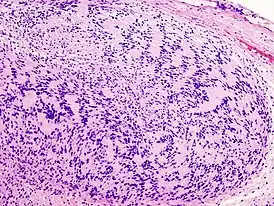

![]() Микропрепарат опухоли окраска гематоксилин-эозин. | |

Невринома состоит из веретенообразных клеток с палочкоподобными ядрами. Клетки и волокна опухоли образуют «палисадные» структуры (ядерные палисады, тельца Верокаи) с участками, состоящими из волокон[2].

Традиционно различают два гистологических типа неврином: тип Верокаи, или тип А, и тип Антони, или тип Б. Данное разделение условно и практического значения для диагностики не имеет. Советский нейрохирург, академик АМН СССР Б. Г. Егоров при исследовании неврином слухового нерва обнаружил, что их структурное многообразие зависит не от свойств опухолевой ткани, а от деструктивных и рубцовых процессов[1].

Микроскопическое строение опухоли на разных стадиях роста может быть различным в зависимости от интенсивности дистрофических процессов и нарушений кровообращения. Нарушения кровообращения сопровождаются скоплением гемосидерина и разрастанием фиброзной ткани. Всё это создаёт пёструю гистологическую картину[1].